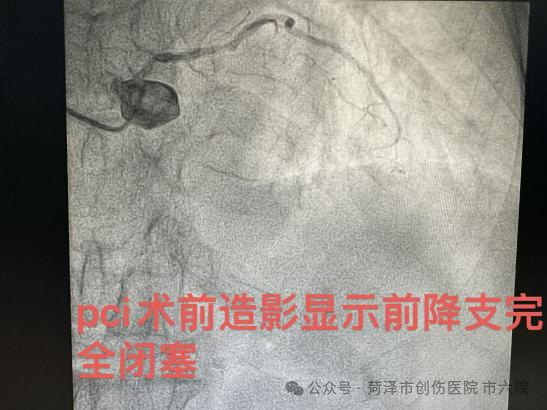

该患者因频繁胸痛于菏泽市创伤医院(市六院)心内科治疗,张吉宏主任为其造影后确诊为三支病变,左主干病变,前降支闭塞,对角支次闭塞,病情十分危重。考虑到患者年龄较大,介入风险极高,建议家属行心外科搭桥手术。

10日下午,联勤保障部队第九六〇医院介入诊疗团队抵达医院,在专家团队的加持下,患者经过两小时的介入治疗,手术获得圆满成功,分别于前降支置入支架三枚,回旋支置入支架一枚,血管内超声显示支架贴壁良好,冠脉三级血流恢复,症状完全缓解,术中患者全程意识清醒,生命体征平稳,无明显不适。“不用开胸搭桥,多受罪了!,谢谢你们!”得知手术顺利完成,患者家属十分感激地说到。